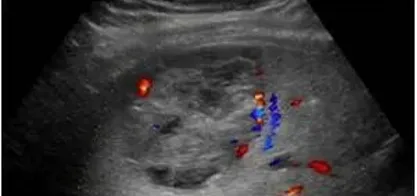

肝局灶性结节增生(FNH)

● 超声表现

(1)大部分形态规则(类圆形)、边界清,低或稍低回声或等回声为主,高回声少见,合并脂肪肝时,基本为低回声。

(2)回声均匀或不均匀,少部分中央可见星状或条状低回声,部分周边见低回声晕环(容易误诊为恶性)。

(3)CDFI:血流丰富,病灶可探测到一支血流由病灶外部进入病灶内(即滋养动脉),典型的呈轮辐状血流(但文献报道检出率低,仅20%可检出)。